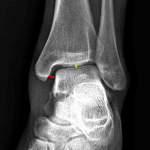

Sample ReportMild medial clear space widening without acute fracture identified. Recommend dedicated leg radiographs to look for proximal fibular fracture.

Mild soft tissue swelling overlying the lateral malleolus.

Joint spaces are maintained.